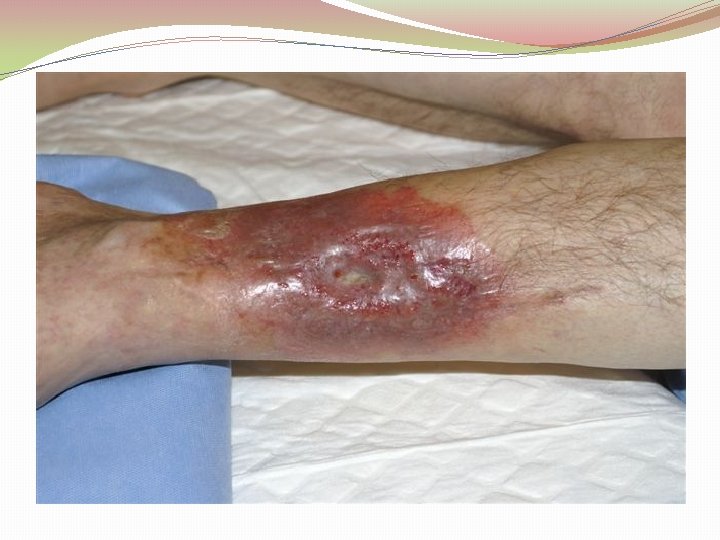

Ķirurģiska ārstēšana Osteomielīta pacientiem jāveic radikāls debridement ķirurģiski, kas ietver visu procesā iesaistīto audu rezekciju: �Mīksto audu rētas rezekcija �Cīpslu kalcinātu rezekcija �Distantu sekvestru rezekcija �Kaula rezekcija līdz vizuāli veseliem audiem – readzama punktveida asiņošana ´Paprika sign’. Bogdan Maciuceanu, Lucian Jiga, Alexandru Nistor, Jenel Marian Pastrascu, Mihail Ionac Chronic Osteomyelitis of Long Bones Timisoaral Medical Jornal, 2005

Ķirurģiska ārstēšana Veiksmīgas ķirurģiskas ārstēšanas stūrakmens ir mirušas telpas ‘Dead space’ aizpildīšana, kas izveidojas pēc debridemet veikšanas Brad Parsons, Elton Strauss, Surgical management of chronic osteomyelitis, The American Journal of Surgery 188 (Suppl to July 2004) 57 S– 66 S